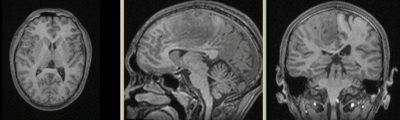

this is the fixed reference image. All images are aligned into this space lleft this is the T2 reference image, serves as target to the DTI baseline, but is itself aligned to the SPGR lleft DTI Baseline this is the DTI tensor image, in the same orientation as the DTI Baseline

T1 SPGR

fixed image 1

T2

DTI baseline

DTI tensor

This is a classic case of a multi-sequence MRI exam we wish to spatially align to the anatomical reference scan (T1-SPGR). The scan of interest is the DTI image to be aligned for surgical planning/reference. The key points are: 1) the DWI sequence (EPI) contains distortions we seek to correct via non-rigid alignment; 2) the DTI baseline is similar in contrast to a T2, albeit at much lower resolution, but we do not have a T2 weighted anatomical scan, but instead a T1 and a FLAIR. So we use the FLAIR as the fixed image, because its contrast matches the DTI-baseline better than the T1, esp. in terms of tumor contrast.